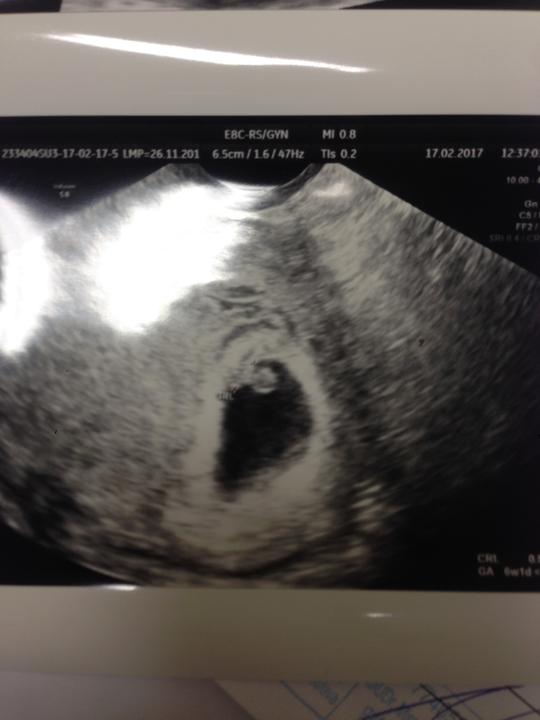

...Deň za dňom ubiehali ako voda pomedzi prsty, rany na duši sa zahojili a ja som sa znovu začala psychicky a fyzicky pripravovať na ďalší boj, ktorý ma čaká. Vianočné sviatky prefrčali rýchlosťou blesku, privítali sme nový rok a s ním znovu prišli na rad ďalšie dávky liekov...

..9.januára 2017 som za pochodu s Fraxiparinom začala brať Proveru. Zdravo som sa stravovala, neprepchávala som sa aj keď jednej sladkosti denne som sa nevedela vzdať (aspoň jeden malý štvorček čokolády musel byť) a viac som pila tekutiny a aj fyzická aktivita patrila k mojej dennej rutine. Zároveň som aj naďalej užívala vitamíny. No aj keď som bola na tento boj pripravená bála som sa... Čoho??? Bála som sa predčasného konca...Nejakej komplikácie...Napríklad takej aká nastala pri prvej stimulácii.

...16. januára 2017 ku Fraxiparinu a Provere pribudol Decapeptyl. Zo začiatku každá ďalšia injekcia, ktorú som si pichla ma bolela viac ako tá predtým. Začalo mi to robiť problémy a nevedela som, ako si vydržím pichať dve a neskôr až tri injekcie denne ďalšie asi 4 týždne, keď už teraz moje sadielko na bruchu akosi nechce prijímať ihly a vzpiera sa. Robili sa mi modriny a nahmatávala som si hrče. Nevedela som, kam si ich môžem pichnúť. Časom sa ale tieto pocity potlačili do úzadia mojej mysle a bolesť som začala prehliadať...

Ako predtým, tak aj teraz ma viac trápila rastúca pneumatika na bruchu a stúpajúca ručička na váhe a tak som si začala hovoriť, že keď v zdraví prežijem toto obdobie, tak sa teším ako začnem chodiť do fitka lebo teraz vyzerám ako veľryba (a to som si nechcela radšej ani predstaviť ako budem vyzerať keď mi bude dopriate a budem tehotná). Vedela som, že za moje priberanie môžu hormóny, ktoré som do seba pchala, lebo som si dávala pozor na to čo jem, no radšej som sa nepozerala do zrkadla dlhšie ako bolo nutné (nech ma z toho zbytočne nechytajú depky) a už som sa radšej nevážila (aby ma z toho čísla rovno nevykotilo) a vravela som si, že to je iba malý detail a sprievodný jav toho môjho boja, ktorý onedlho skončí.